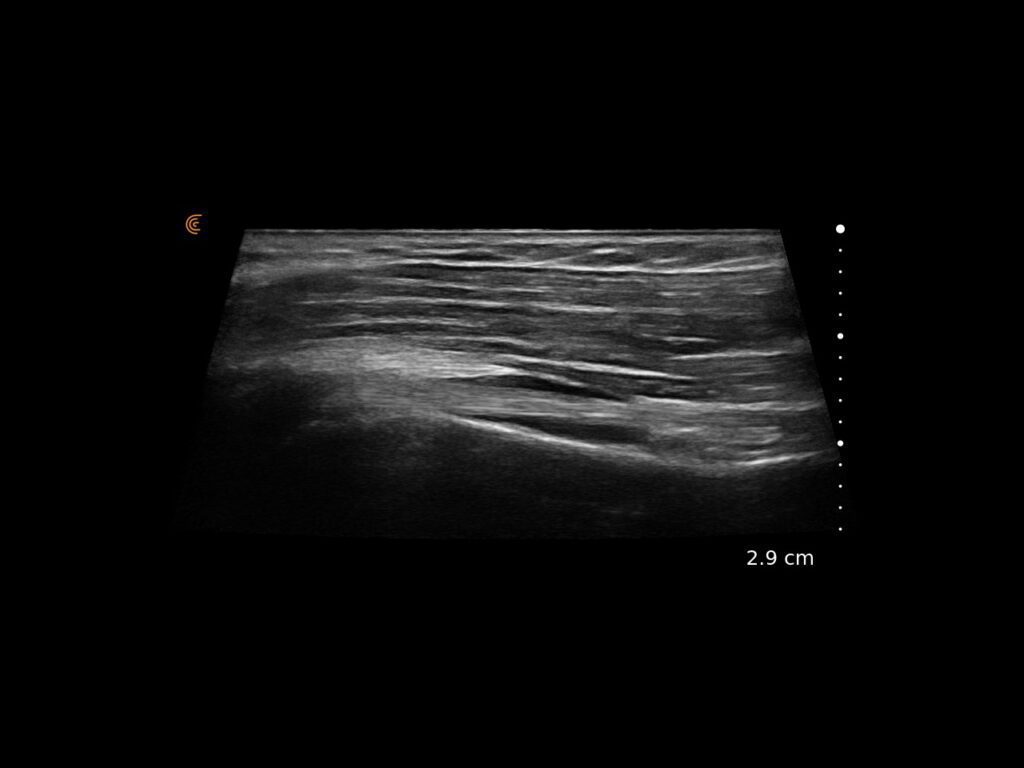

Get Athletes Back in Action – Faster.

Specialized presets and high resolution provide fast, accurate imaging for athletes’ needs.